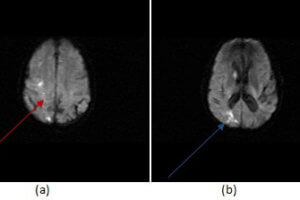

Watershed Infarct

The anterior middle and posterior cerebral arteries supply the majority of the cerebral cortex. However, thin regions of brain at the junction of these vascular territories are relatively under supplied by blood... Read more »